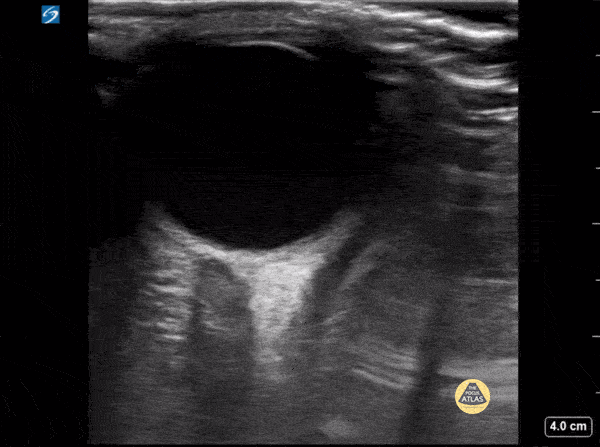

Peds-Orbital - Normal ONSD

8 year old female presented with headache for 3 days, ocular ultrasound revealed no increased optic nerve sheath diameter. Measured 3 mm from the posterior border of the eye, the diameter was 3.7 mm, and there was no visualized crescent sign. Contributor: Zach Boivin, MD, @ZachBoivinMD